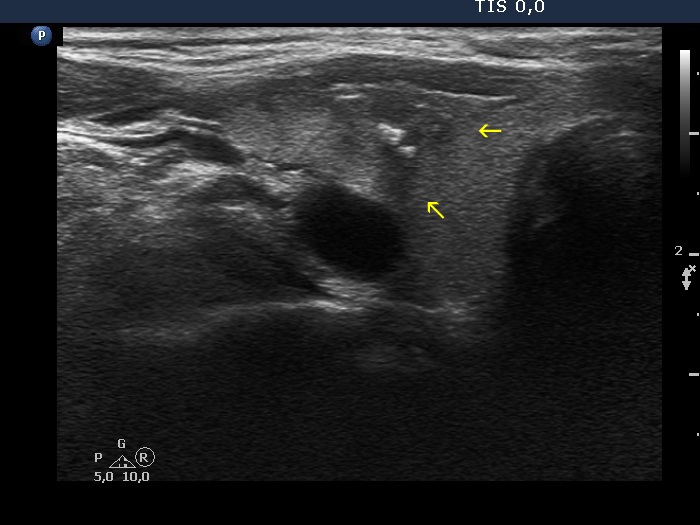

Right lobe, transverse scan. Yellow arrows point to lobulations.